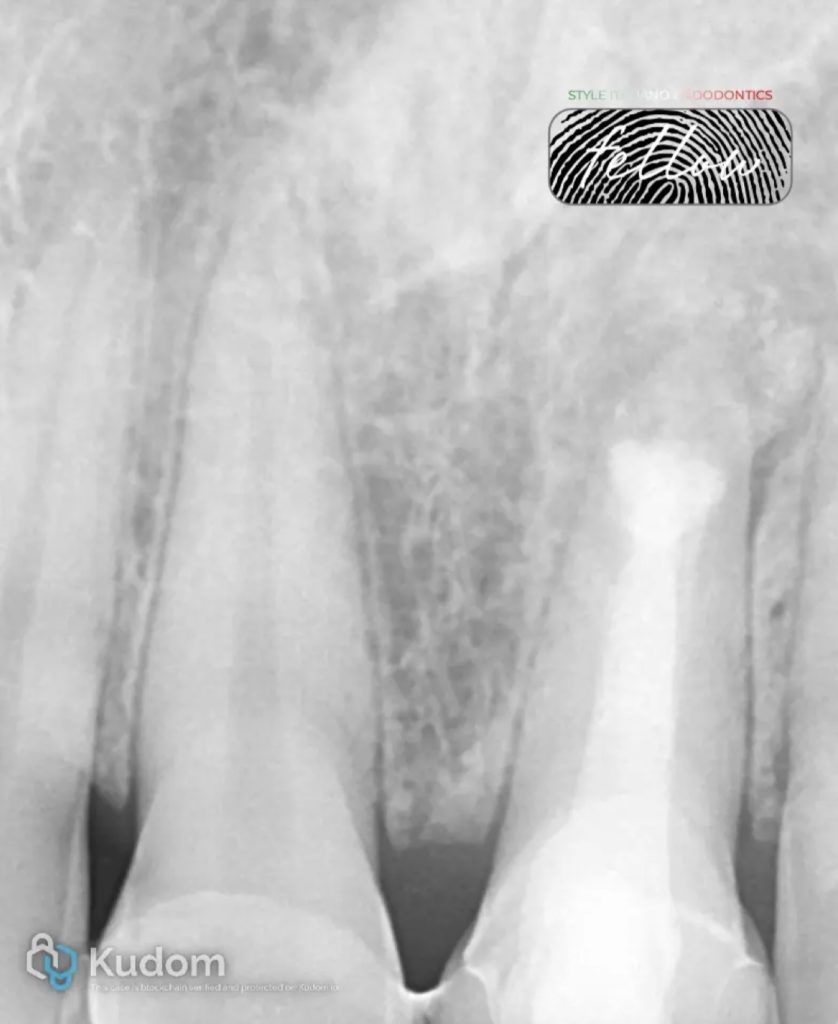

The CBCT revealed poorly done obturation with no apical seal, extruded obturation material in the periapical area, and a large periapical lesion. The lesion measured 15mm mesiodistally, 9 mm apico-coronally and 9 mm labio-palatally.

Fig. 3

The periapical lesion had extended lingual to the maxillary central and lateral incisors. The loss of the buccal bone plate was evident. The extensive inflammatory root resorption resulted in an acute-angled buccal bevel to the root tip of the maxillary left central incisor.